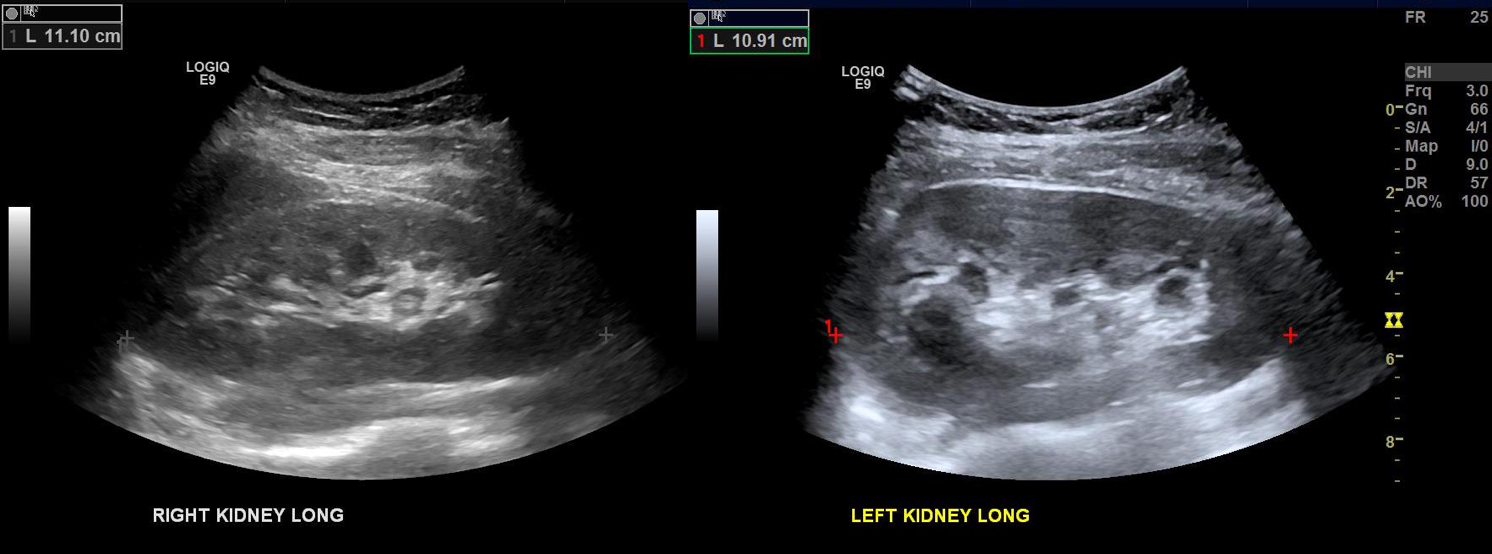

The patient is a young woman in her twenties who developed severe right sided abdominal and back pain about 4 months prior to presentation associated with bouts of bloody urine. Activity and standing exacerbated her pain and inactivity and recumbency relieved it. She gained 15 pounds because of her inactivity. Examination was significant for tenderness over her left kidney. Urinanalysis showed positive proteinuria and hemaglobinuria.

On the duplex, the proximal left renal vein (LRV) was not visualized. The right kidney had normal parenchymal appearance and blood flows, while the left, the kidney appeared distended and had flows consistent with outflow obstruction.

Duplex kidneys bmode

The left kidney is swollen and tender.